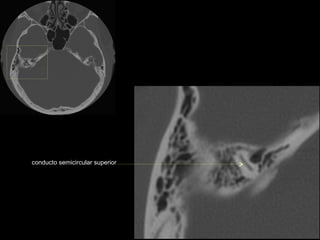

CATEDRA DE RADIOLOGIA U.N.L.P.   Hueso temporal normal              Edición 2002

seno maxilar

conducto

carotídeo

auditivo externo

protuberancia

occipital externa

trompa de Eustaquio

conducto auditivo externo

celdillas mastoideas

eminencia piramidal

seno timpánico

receso del n. facial

nervio facial (3era)

estribo (cruras)

nervio facial

ventana oval

martillo

yunque

cóclea

vestíbulo

conducto semicircular externo

articulación yunque/martillo

conducto auditivo interno

conducto semicircular posterior

antro mastoideo

celdillas retrolaberínticas

conducto semicircular

superior

conducto semicircular superior